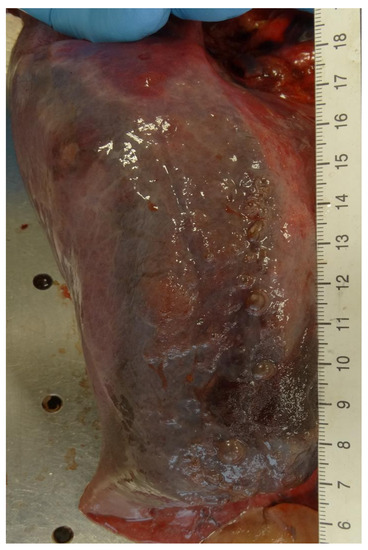

2.2.2. Internal Examination